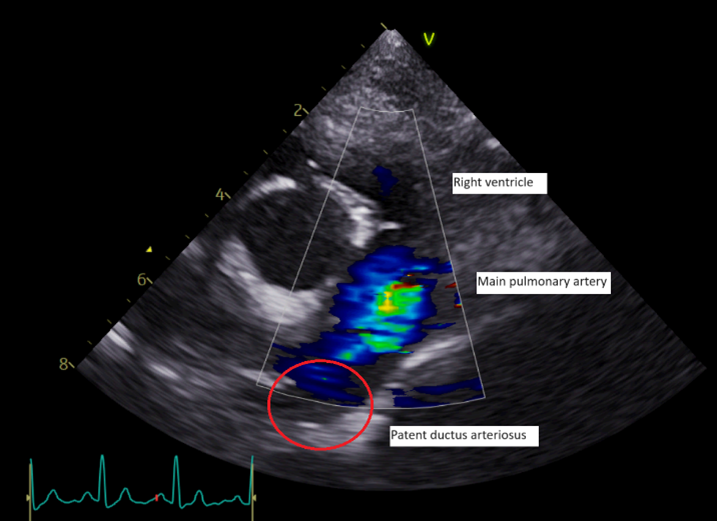

Echocardiographic findings

Echocardiographic visualisation of the PDA is the most common diagnostic tool (Figure 2).

In dogs with left-to-right PDA, the defect can be indirectly appreciated by the presence of a continuous turbulent flow in the main pulmonary artery. Secondary changes linked to left-to-right PDA include left atrial and ventricular dilation with or without mitral regurgitation and possible signs of left-sided CHF. The systolic function of the left ventricle is usually preserved, and the pulmonary arteries are dilated. Pulmonic insufficiency is also common. Measurements of the ostium and the ampulla are often required to plan surgical procedures.